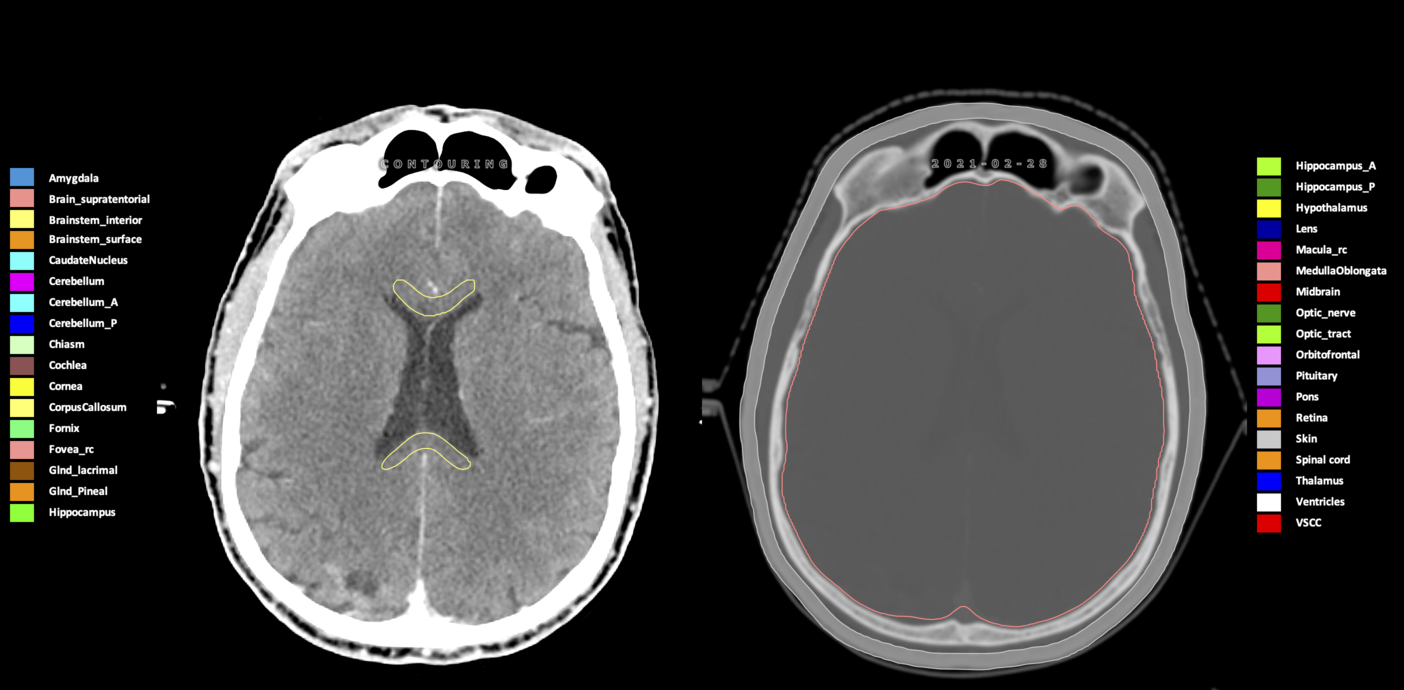

Included are all OARs known to be relevant for radiation-induced toxicity in neuro-oncology: brain, brainstem (midbrain, pons, medulla oblongata), chiasm, cerebellum (anterior & posterior), cochlea, cornea, hippocampus (anterior & posterior), hypothalamus, lens, lacrimal gland, optic nerve, pituitary, skin, and vestibular & semicircular canals. To further facilitate research on cognition, vision and radiological changes after irradiation of the brain, potential clinically-relevant OARs are included: amygdala, caudate nucleus, cerebellum (anterior & posterior), corpus callosum, fornix, macula, optic tract, orbitofrontal cortex, periventricular space (PVS), pineal gland, and thalamus.

Three-dimensional delineation of the 25 consensus OARs for neuro-oncology are shown on CT (WW/WL 120/40, 3000/600), 3T MR images, (T1Gd, T2FLAIR 1mm) and 7T MR (MP2RAGE 0.7 mm). All are presented in transversal, sagittal and coronal view.